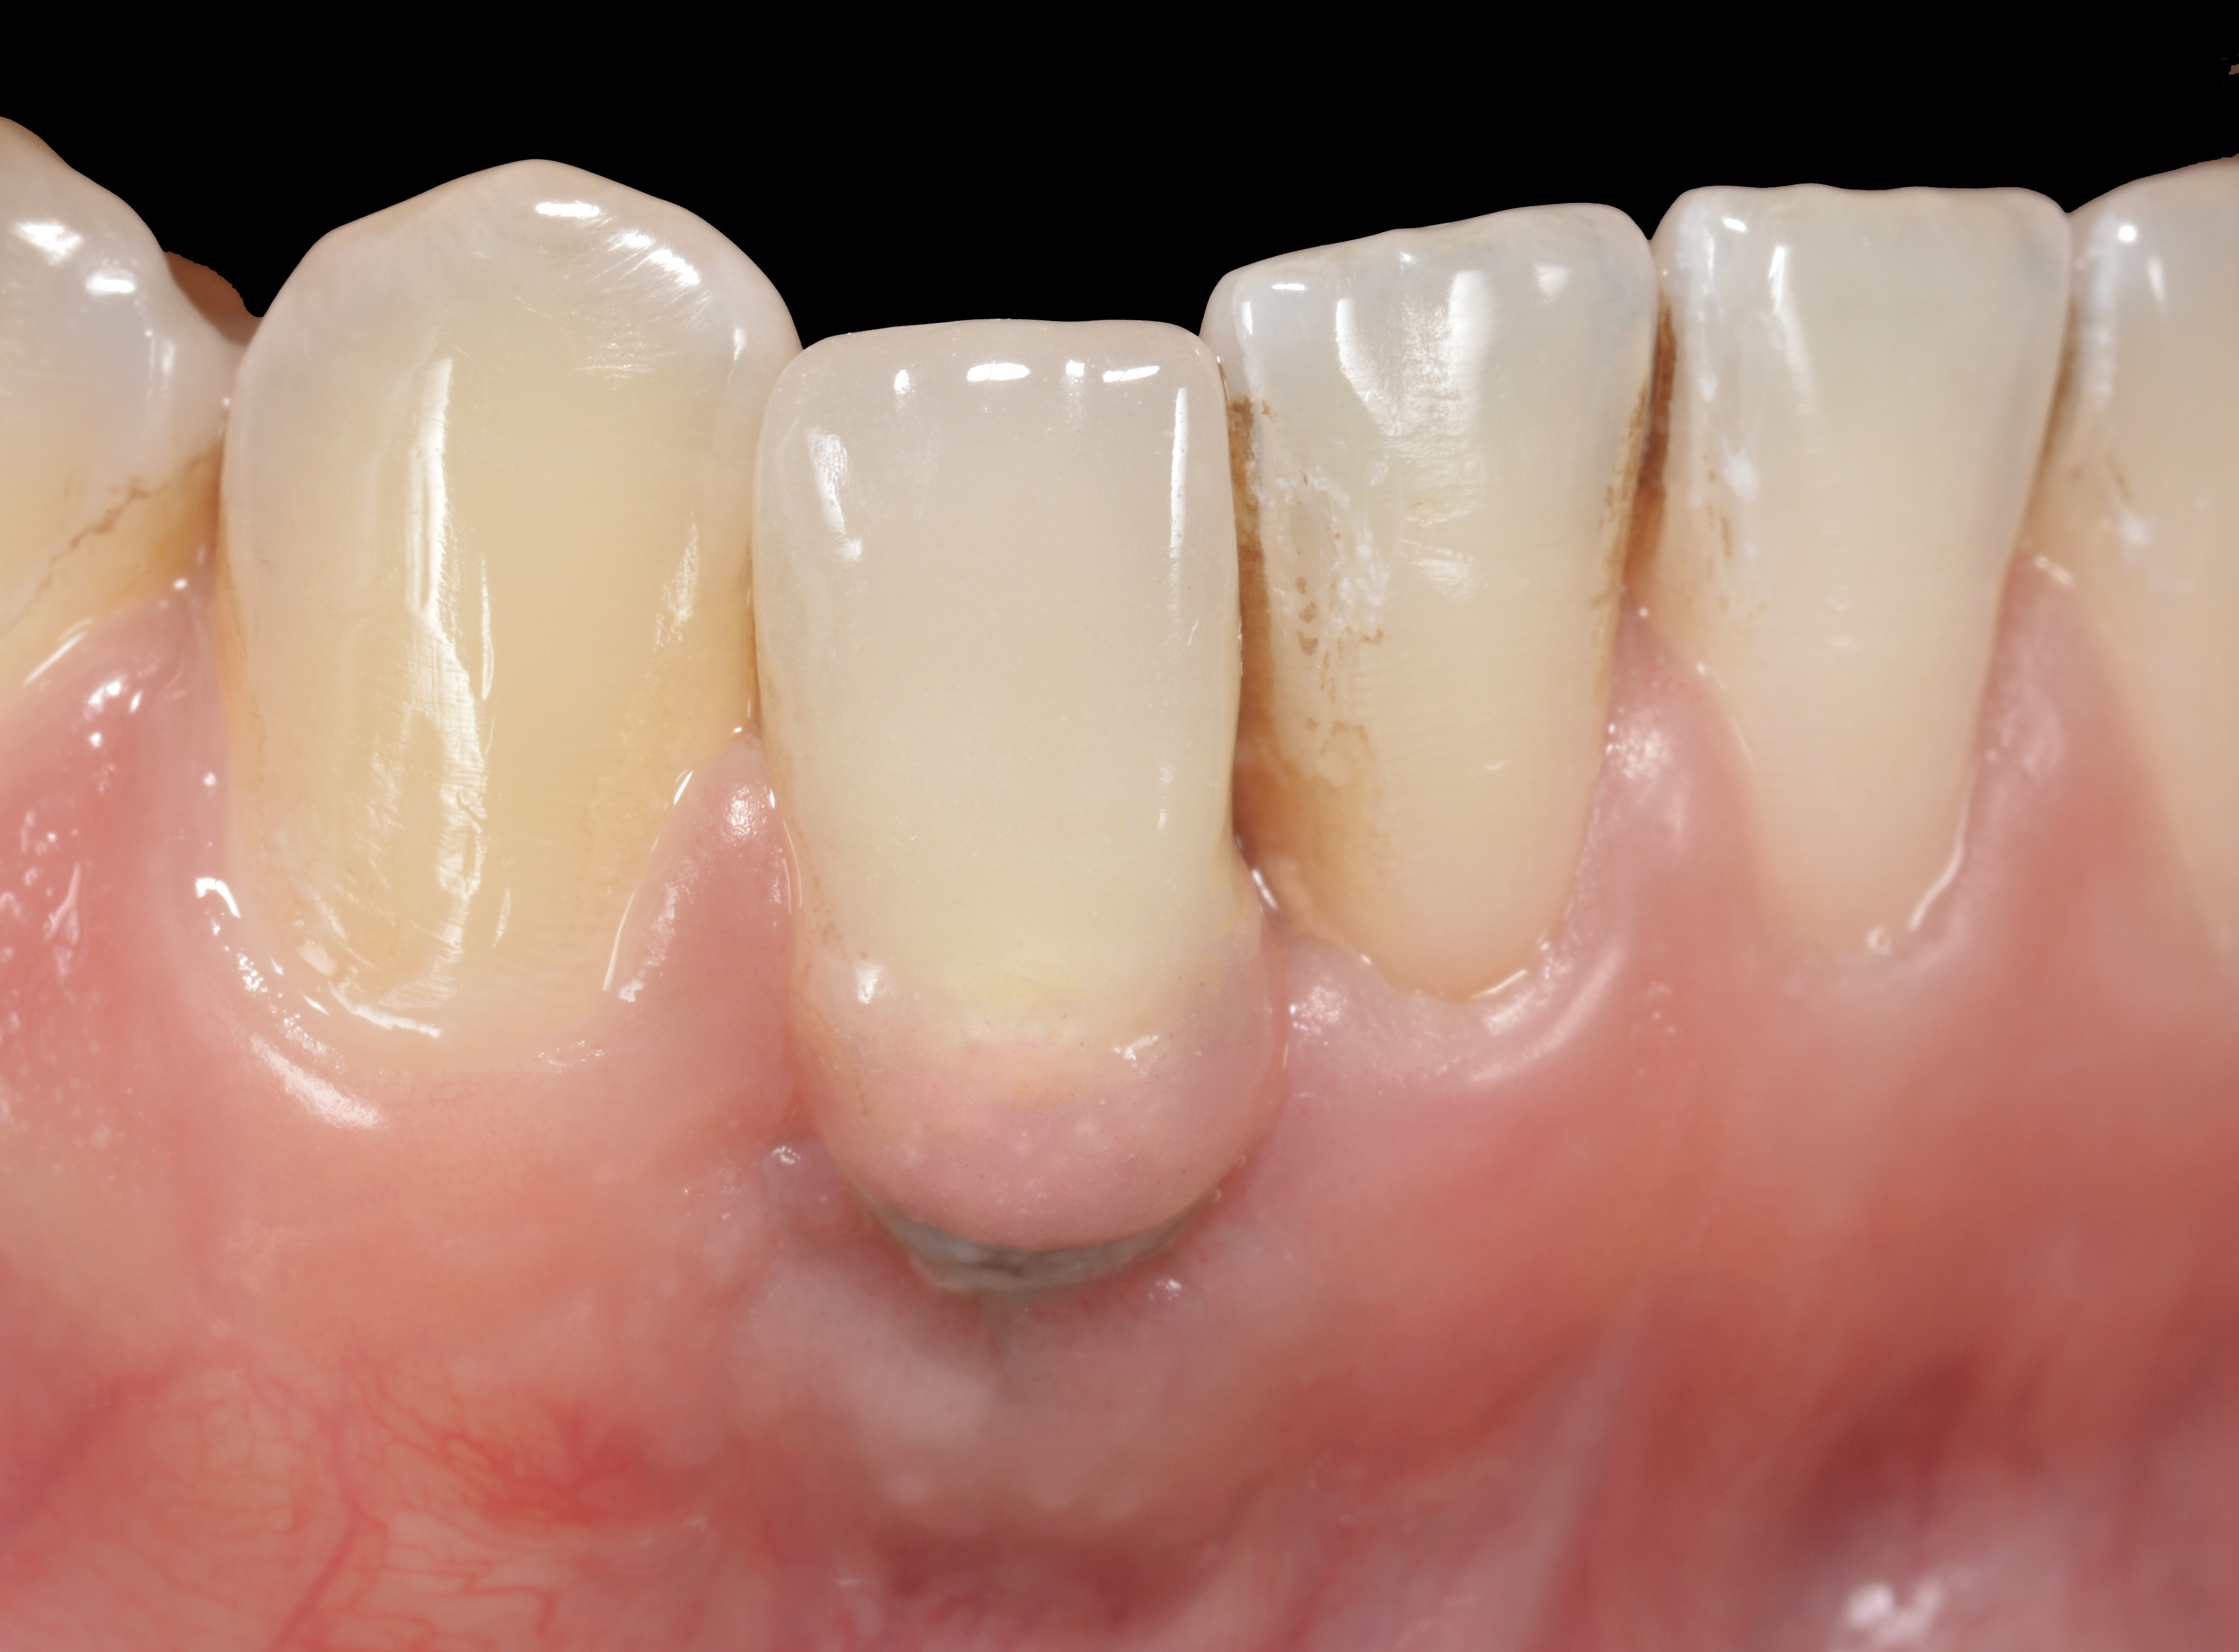

Fig 3. A patient presented with a high smile line and midfacial recession of the maxillary right lateral incisor as evidenced by the increased tooth length compared with the contralateral lateral incisor.

Figure 3

Fig 4. Intraoral view of tooth No. 7 with the gingival zenith more apical than the adjacent central incisor and canine tooth.

Figure 4